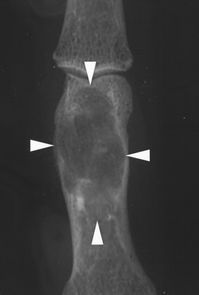

内生软骨瘤:在长骨的X射线照片上,软骨瘤很少与巨细胞瘤混淆,但是在手和脚的小骨(图4)中区分这两种疾病可能会有点难度。两种肿瘤看起来都可以是纯粹溶骨性改变,并且涉及小骨的大部分体积,包括关节下部分。然而,软骨瘤的边缘通常是硬化的,除非骨折,否则软骨瘤是无症状的[2]。

图4.-内生软骨瘤。52岁男性的射线照片显示,中指近节指骨病灶轻度膨胀生长,边界清晰,且有硬化(箭头)。